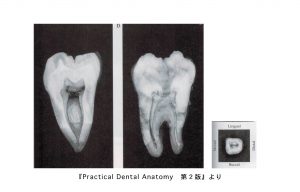

下顎第二大臼歯の中身

• 歯の外形を縮小した形。

• 髄室角の突出は第一大臼歯より弱い。

• 根管の数は2〜4根管で通常は3根管が多い。近心根は2根管性(70%)、遠心根は1根管性が多い。

• 頬側根管は細く彎曲するものから幅広いものまで認められる。

• 隣接面からみると、舌側根管は舌側に凸彎し、頬側根管は頬側に凸彎している。